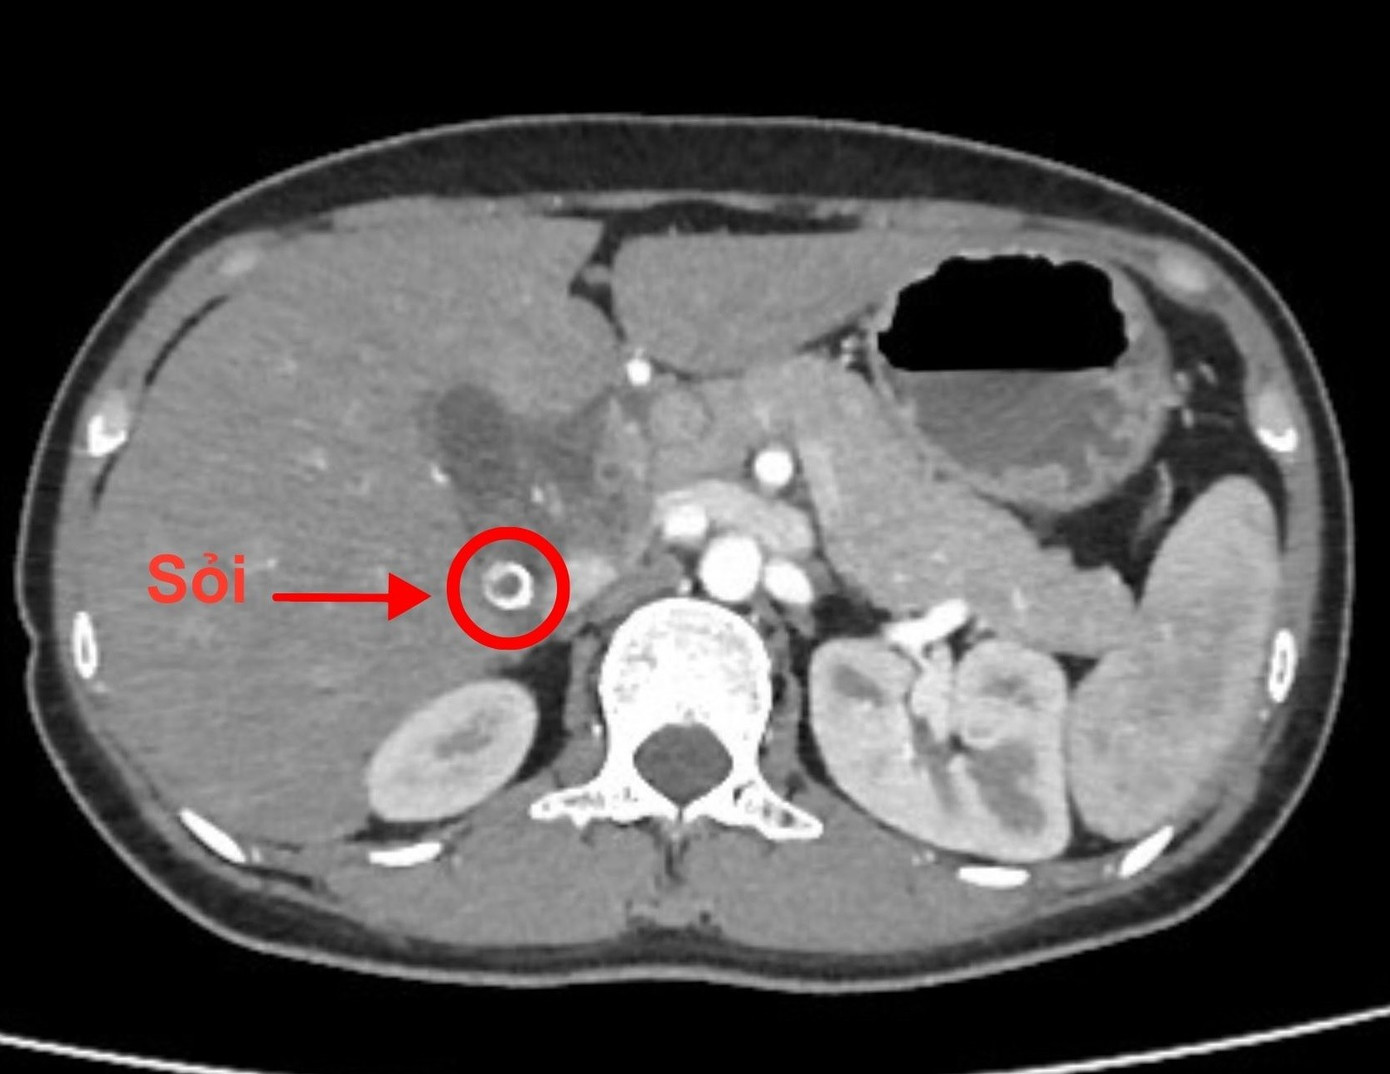

Trên hình ảnh chụp CT, các bác sĩ phát hiện túi mật bệnh nhân chứa đầy sỏi

Tại đây, các bác sĩ ghi nhận tình trạng người bệnh diễn tiến nhanh, có dấu hiệu nhiễm trùng nặng. Kết quả xét nghiệm cho thấy men gan và bạch cầu đều tăng cao. Hình ảnh chụp MSCT phát hiện sỏi ống mật chủ gây giãn đường mật trong và ngoài gan, kèm túi mật căng to, chứa nhiều sỏi. Đây là tình trạng nguy hiểm, có thể dẫn đến nhiễm trùng huyết, suy gan nếu không xử trí kịp thời.